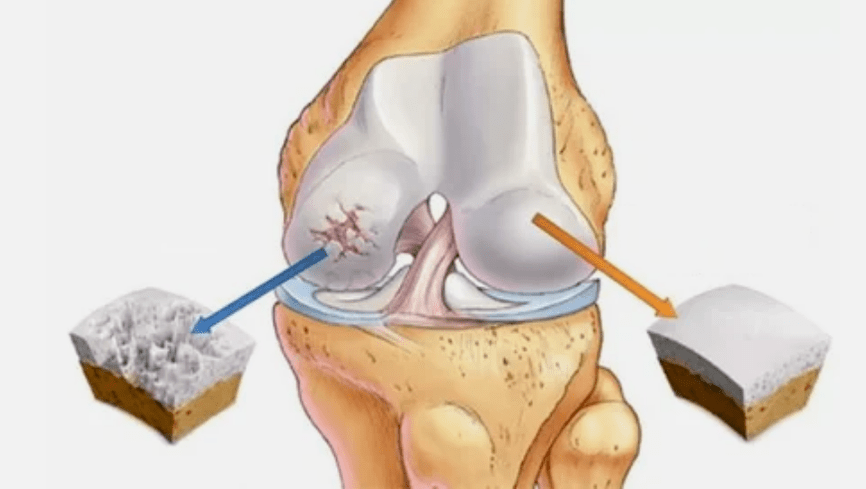

- Die primäre Läsion beeinflusst den hyalinen Knorpel. Bei Kreislaufstörungen tritt eine Verschlechterung der pathologischen Kraft auf. Es ist der erste Schritt oder die erste Ursache, die Arthrose auftreten kann.

- Hyalin -Beschichtungspathologien. Die Ausdünnung des Knorpels führt zum Ersatz seiner pathologischen Gewebe - Knochenstrukturen.

- Anomale Wachstum erscheinen auf Knorpel - Osteophyten.

- Die auftretende Verletzung der natürlichen Anatomie des Knorpels und der Knochen führt zu der Überlastung gesunder Knorpelbereiche. Die Zerstörung von Gelenkgeweben ohne Behandlung führt ständig voran und führt zu Behinderungen.

- 1 Grad. Morphologische Störungen haben bereits begonnen, sind aber noch nicht auffällig. Die Pathologie beeinflusst hauptsächlich den Zustand der Synovialflüssigkeit, die schlechtere Knorpelgewebe mit Nährstoffkomponenten liefert und die Stärke des Knorpels verringert. Die Belastung der Gelenke führt zu Entzündungen und Schmerzen.

- Stufe 2. Aufgrund des Versorgungsmangels werden die notwendigen Patronen zerstört. Auf der Oberfläche des Knorpels werden Knochenwachstum gebildet. Die Schmerzen erwerben einen ausgeprägteren Charakter, verstärken sich nach einer langen Pause und werden durch kleine körperliche Arbeit beseitigt. Schmerzen werden von Entzündungen begleitet. Die Muskeln sind gedehnt, was zu schwachen oder durchschnittlichen Beeinträchtigungen der Motorfunktionen führt.